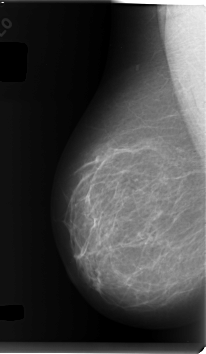

C_0116_1.RIGHT_MLO

RIGHT_MLO LINES 6016 PIXELS_PER_LINE 3488 BITS_PER_PIXEL 12 RESOLUTION 50 NON_OVERLAY